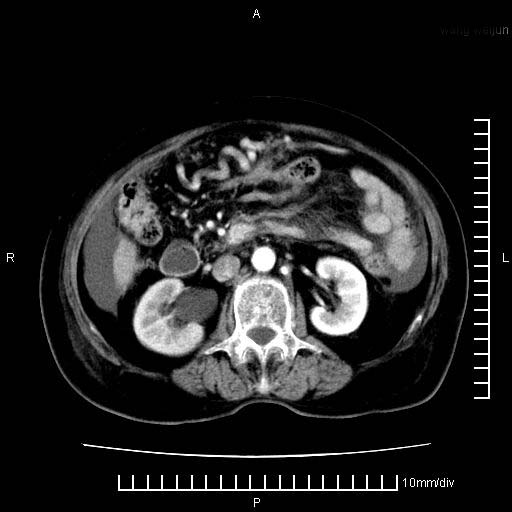

标题: CT28280:腹部增强:女性,80岁

上腹疼痛月余,外院核磁诊断胰腺癌。现临床示右下腹可明显触及包块,可片子上怎么没有看到?

1.胰腺颈体部癌。

2。腹腔积液。

3。右胸腔积液,伴右肺下叶部分萎陷。

4。右肾盂囊肿。

胰腺体部癌累及周围器官,腹膜、粘连

1。胰腺ca伴腹膜腔转移

2。肝左叶低密度灶,考虑转移可能

胰腺结构模糊,胰尾部见囊性包块,周围脂肪密度增高,左肾前筋膜增厚,胸水、腹水。不符合胰腺ca伴腹膜腔转移。考虑胰腺炎伴假性囊肿形成、胸腹腔积液。

右肾盂囊肿。

1)考虑胰腺癌并胰腺假性囊肿形成。2)肝内低密度灶,不排除转移。3)右肾盂积水。4)腹水。5)右侧胸腔积液并右肺下叶部分膨胀不全。